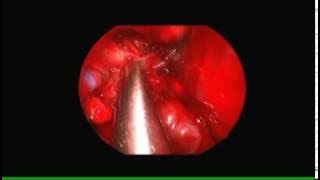

Трансназальное эндоскопическое удаление юношеской ангиофибромы носоглотки и основания черепа.

Операцию выполнил ЛОР-хирург Георгий Полев: https://bit.ly/2GnmgTG Пациент К., 17 лет, в течение года отмечал ...

Ильинская Больница